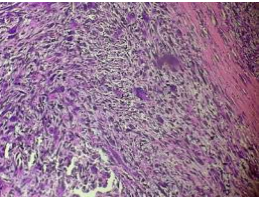

Fig 3. Myxoid Matrix

Fig.4 Pleomorphism

Fig.5 Interlacing fascicles

Post operative period was uneventful. Final histopathology report was suggestive of: tumor type: pleomorphic sarcoma, paratesticular, high grade (FNCLCC score 6), LVSI negative with free margins and no skin involvement. On IHC, tumour cells were immunopositive for desmin, SMA(focally), CK (focally),and negative for CD34, MDM2 and CD68, making the final diagnosis of leiomyosarcoma. Multidisciplinary discussion was done and it was decided to keep patient on observation .